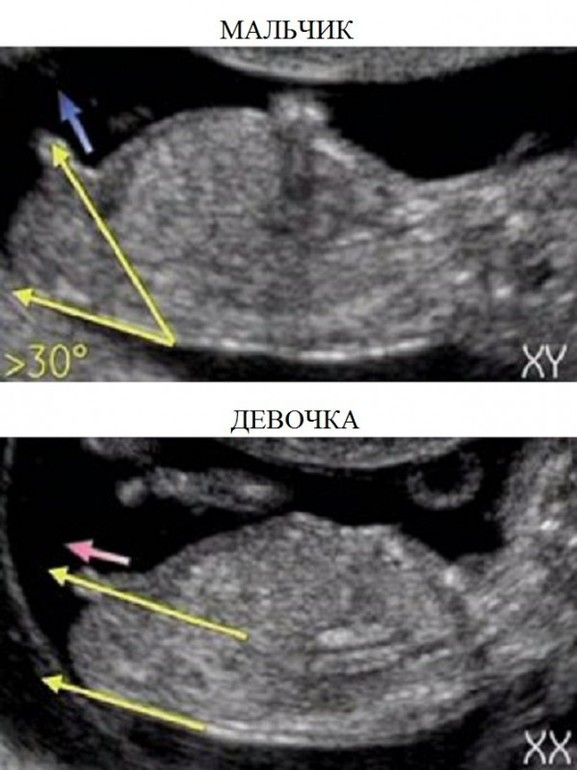

Тут не очень понятно, похоже на девочку. Смотреть на угол лобковой кости, у мальчика больше кверху торчит.

Саша, тут плохо видно, да и я не специалист. Посмотрите в интернете половой бугорок у девочек и мальчиков на узи, там видно различие. Здесь ножка загораживает.

Изображение Здесь нашла на ББ

Изображение Девочка. Вот тут бугорок паралельно на фото